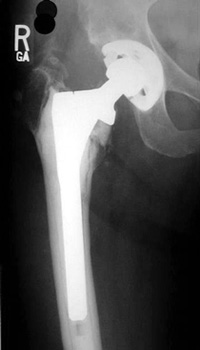

LooseningAs pain and disability due to loosening become severe enough to require revision arthroplasty, abnormalities in the binding of the cement to the bone or prosthesis are almost always visible radiographically. Radiographic abnormalities include:

No prior studies available. Abnormally widened interfaces surrounding entire cement mantle of femoral component, consistent with loosening.